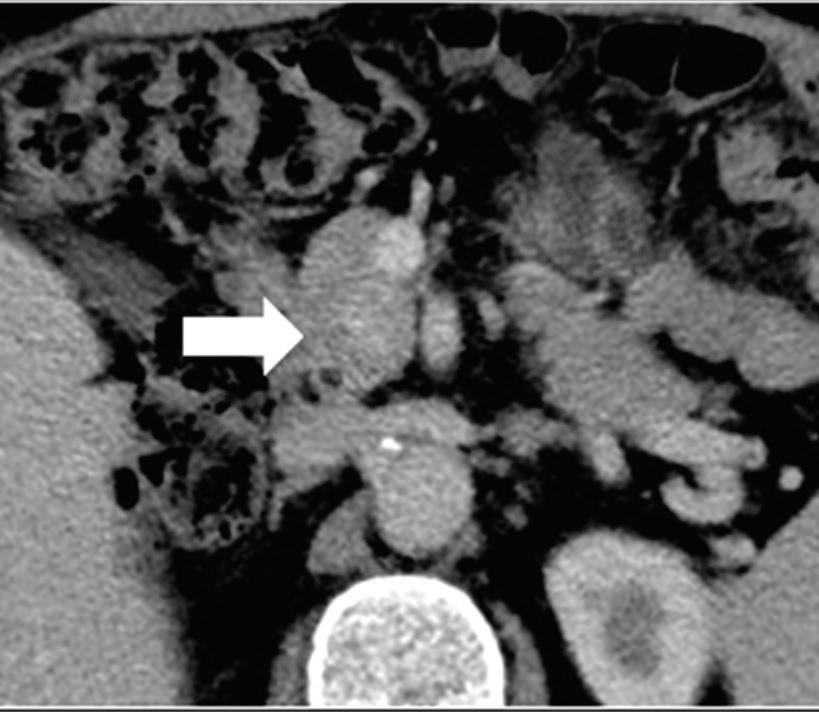

Multifocal HCC treated with sorafenib. (a) A small nodule (arrow) is barely seen on conventional axial CT image, acquired at late arterial phase after administration of 70 ml of contrast material (iodine concentration 350 mg/ml). (b) Monoenergetic 50 keV and (c) Z effective images improve the detection of this small nodule as well as allowing better evaluation of the peripheral solid component of both nodules seen in these images, with a precision comparable to that of (d) post contrast MR image.

A small isoattenuating pancreatic adenocarcinoma (arrow), (a) which tend to blend into normal parenchyma on conventional axial CT image, acquired at pancreatic parenchymal phase with administration of 70 ml of contrast material (iodine concentration 350 mg/ml). (b) Monoenergetic 50 keV and (c) Z effective images improve detection by increasing conspicuity and contrast between tumor and normal parenchyma.

Liver tumors. Use of low-monoenergetic images on late arterial phase improves the detection of hypervascular liver lesions (e.g., HCC in cirrhotic liver) (Figure 4).3,17,52,53 It also improves detection of hypovascular liver metastases on portal-venous-phase.54

Pancreatic tumors. Several studies have demonstrated an obvious advantage of DECT for detection and staging of pancreatic adenocarcinoma using the low-monoenergetic data sets (Figure 5), regardless of the timing of the acquisition applied (single venous phase,55 pancreatic parenchymal phase,56 single split bolus single acquisition57).